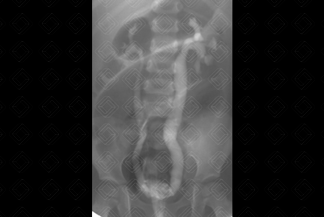

Texto alternativo para a imagem Figura 1. Créditos: Dra. Elazir Mota - Rio de Janeiro/RJ

Descrição das figuras 1 e 2: Fase de enchimento na qual observa-se bexiga opacificada (asterisco) por meio de contraste, onde já visualiza-se o início do refluxo bilateral (setas vermelhas). A radiografia final evidencia fase pós-miccional, com bexiga vazia e acentuação do refluxo vesicoureteral (grau II à direita e grau III, à esquerda). [cms-watermark]